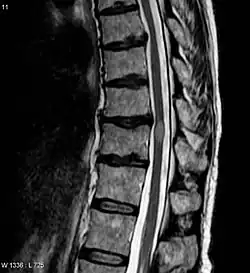

- МРТ всего позвоночника с контрастным усилением и без него (Данное исследование позволит оценить насколько большой очаг поражения, выявить признаки воспаления. А также исключить сдавление спинного мозга, при котором возможно оперативное лечение)

- МРТ головного мозга с контрастным усилением гадолинием и без него. (Для оценки наличия очагов демиелинизации в головном мозге, что может указывать на рассеянный склероз)